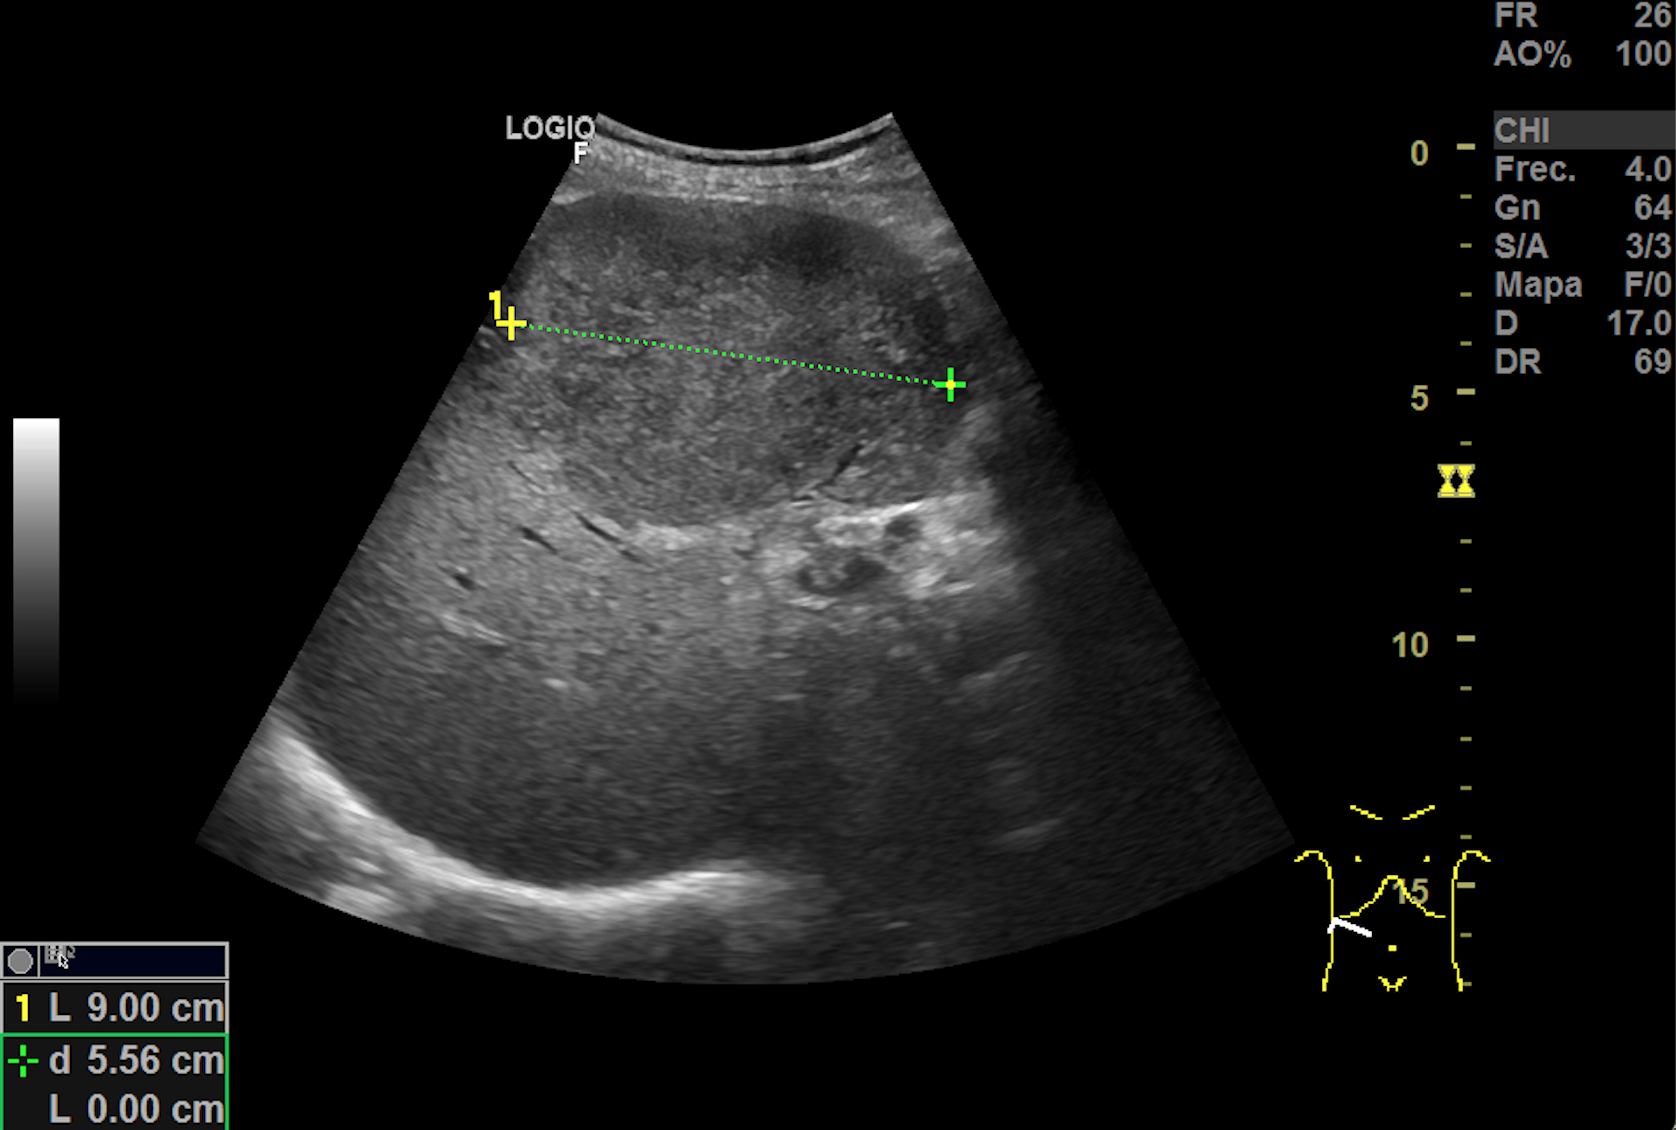

Hallazgos ecográficos

Hígado aumentado de tamaño donde se observan, ocupando gran parte del lóbulo hepático derecho al menos 2 imágenes redondeadas heteroecoicas vascularizadas de hasta 11 cm de diámetro. Vesicula bien replecionada con imagenes heteroecoicas con sombra posterior en su interior. El hemiabdomen izquierdo esta ocupado por lesiones anecoicas que impresionan de quistes renales. No observamos líquido libre.

TAC body: Masa subcarinal que contacta con esófago. Hepatomegalia con 2 lesiones focales de gran tamaño en cúpula de 10 x 12 cm y segmento V-VI de 10 x 7,8 cm. Numerosas adenopatias retroperitoneales y en hilio hepático. Vesicula biliar con colelitiasis. Riñón izquierdo con 2 quiste corticales de gran tamaño (13 cm cada uno).